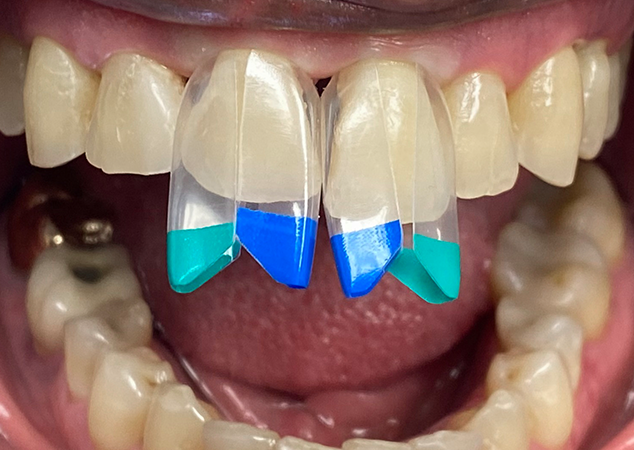

Onto restoring tooth 21. Bioclear blue and green large black triangle matrices brace the tooth on the mesial and distal. This forms the Bioclear aquarium into which the injection moulding takes place. In addition, matrices brace the adjacent teeth in order to preserve their upcoming and final shapes. We call these shield matrices (Fig 6).

FIG. 6

La dent 11 est d'abord préparée, moulée par injection et taillée à 80 % de sa forme finale. La dent 21 est modifiée pour s'adapter aux exigences

de la restauration finale. En raison du décalage de la ligne médiane, la matrice mésiale est stabilisée à l'aide de la méthode de l'entretoise de contact latérale.

Afin de recréer une nouvelle ligne médiane, un étai de contact latéral est réalisé sur la face mésiale de la dent 21 (Cliquez ici pour en savoir plus sur l'étai de contact direct Bioclear). Cela recrée instantanément un point de contact entre les dents 11 et 21, ce qui sert à stabiliser la matrice sur la face mésiale de la dent 21 (Fig. 6).